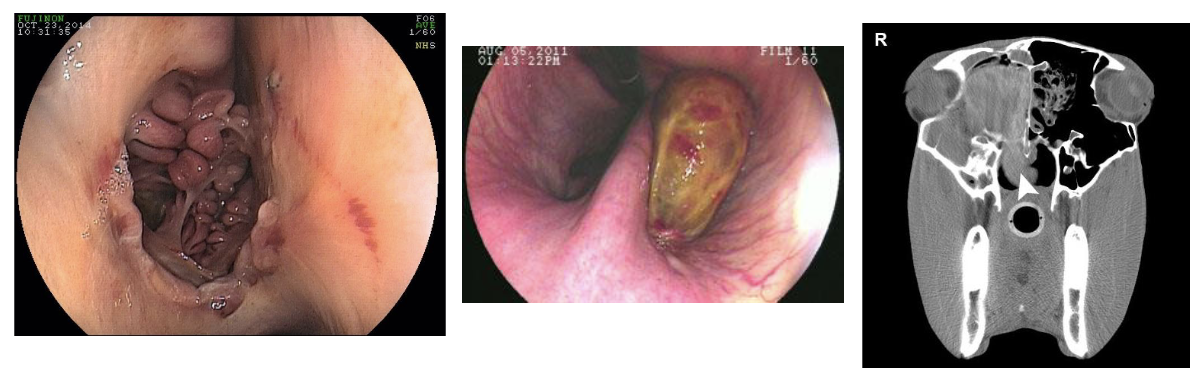

what is this

cecal impaction

sx→ typhlotomy

small intestine distension

blown up w/ fluid & gas, always feels abnormal (normally its smooth, texture is abnormal)

enterolith

stones of calcium and magnesium in intestine, common in southwest, usually in right dorsal colon theyre single